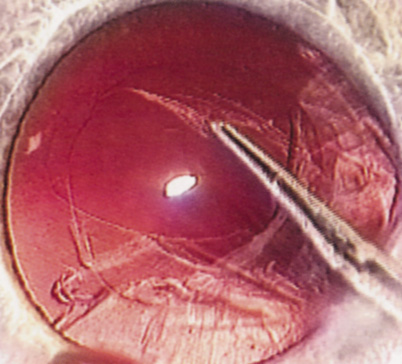

HYDRODISSECTION

Hydrodissection can be performed after the surgeon has successfully completed capsulorrhexis.97 If the capsulorrhexis is not intact, fluid forced around the interior of the capsule may cause the bag to splay open. With capsulorrhexis, hydrodissection is a safe and extremely useful maneuver. Hydrodissection can be thought of as two maneuvers: hydrodelineation and cortical cleaving hydrodissection. By placing a 27-gauge cannula on a syringe filled with balanced saline solution (BSS), the surgeon can direct fluid beneath the residual anterior capsular rim to create a cleavage plane. Depending on the direction the fluid wave takes, different lamellae of the cataract will be separated. Hydrodelineation is the term used when the cleavage plane separates the adult nucleus from the fetal nucleus or the adult nucleus from the more peripheral epinucleus. Hydrodelineation often results in the characteristic golden ring sign (Fig. 11). Cortical cleavage occurs when the cortex is separated from the capsular bag (Fig. 12). Finding the cortical cleavage plane may be facilitated by gently lifting the capsular margin away from the cortex with the BSS cannula before injecting. Several small bursts of fluid allow the surgeon to monitor progress of the fluid wave. When dealing with a soft nucleus, the authors strive to perform true cortical cleaving hydrodissection. For a hard nucleus, hydrodelineation allows manipulation of less of the nuclear bulk, although the remaining epinuclear shell must be addressed in an additional step. Hydrodelineation is particularly useful if the nucleus is not freely mobile after cortical cleaving hydrodissection.

Fig. 11. A crisp “golden ring” is seen from the fluid cleft between the epinucleus and nucleus with hydrodelineation.